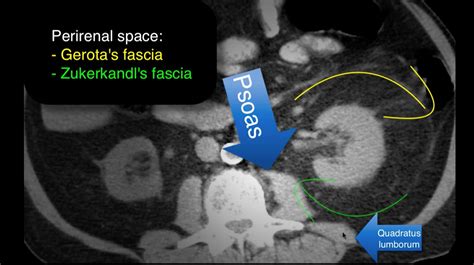

The perirenal fascia of Gerota is a dense layer of connective tissue that encloses the perirenal fat, the kidney, and the suprarenal (adrenal) gland. It is not merely a single sheet but rather a complex arrangement of anterior and posterior lamellae. Anatomically, these two layers fuse at different borders to create a contained space known as the perirenal space.

• Posterior Layer: Also known as the fascia of Zuckerkandl, this layer attaches firmly to the fascia covering the psoas major and quadratus lumborum muscles.

• Lateral Fusion: The anterior and posterior layers fuse laterally to form the lateroconal fascia, which blends with the pararenal fascia.